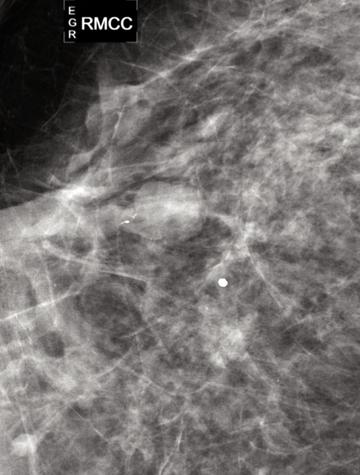

L’écoulement mamelonnaire se rencontre chez 3 à 10 % des femmes qui consultent pour une anomalie. La cause est le plus souvent bénigne (papillome). La probabilité de cancer augmente quand l’écoulement est clair, ou hématique, ou associé à une masse palpable. Les examens complémentaires ont pour but d’affirmer l’existence d’une lésion et d’approcher sa nature. L’IRM est une indication émergente quand l’imagerie conventionnelle est normale.

L’écoulement mamelonnaire se [...]